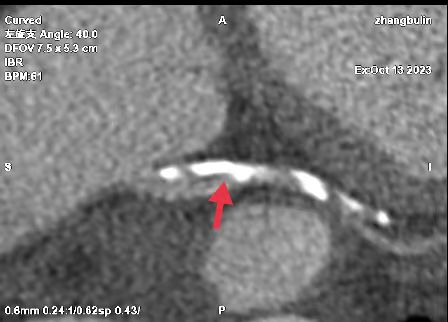

01、**男士,61岁

于2023年11月9日在邯郸仁泰东区体检,冠脉CTA检查提示:冠脉分布呈右优势型。左冠状动脉主干起自主动脉左窦后上方,随即分支为左前降支及回旋支。左、右冠、回旋支及部分分支多发大小不等钙化斑块,局部管腔均呈不同程度狭窄,前降支近、中段、回旋支中段、右冠中段局部管腔均达重度狭窄。首次回访2023年11月10日,通知客户到三甲医院进一步检查和治疗。2023年11月24日跟踪回访,客户已在北京某三甲医院完成支架手术。